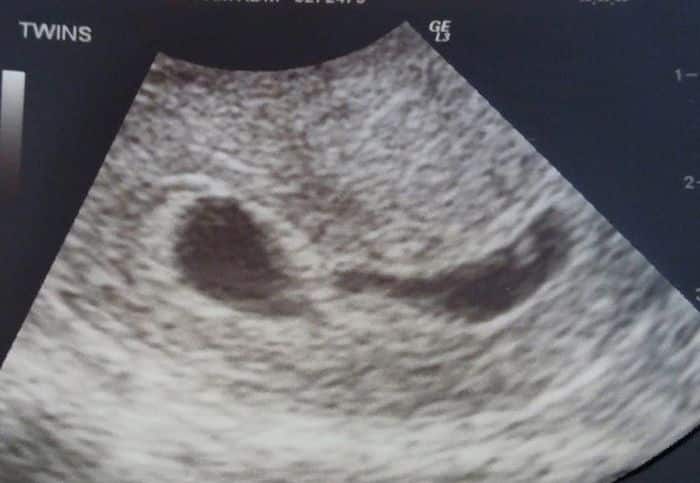

What Does an Ultrasound Look like at 6 Weeks Pregnant With Twins?

The earliest your doctor would likely order an ultrasound confirming twins would be 4 weeks pregnant. But unless you are going through fertility treatments, doing an ultrasound before 6 weeks isn’t very common, with the exception of complications. Women who are going through fertility treatments or have early complications may be able to have an early twin ultrasound at 4 or 5 weeks pregnant and find out they are pregnant with twins.

At four to five weeks after a pregnant woman’s last period the ultrasound commonly shows a small collection of fluid within the lining of the uterus that represents the early development of the gestational sac. At about five and a half weeks after a pregnant woman’s last period the ultrasound typically shows a gestational sac and within it we can see a 3-5 mm bubble-like structure, which is the yolk sac. At approximately six weeks after a pregnant woman’s last period, we can see a small fetal pole, one of the first stages of growth for an embryo, which develops alongside the yolk sac. UT Southwestern Medical Center

Yes! You’d need to have an ultrasound at 6 weeks to confirm a twin pregnancy. Your twin belly at 6 weeks may not look like much of a belly at all, so getting in to your doctor for an ultrasound is key to find out if you’re really having twins.